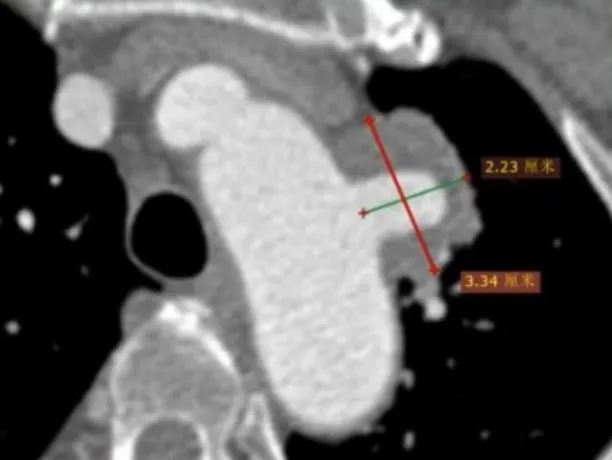

术前检查与评估

增强CTA显示,主动脉弓前壁假性动脉瘤深约2.23cm,基底宽约3.34cm。瘤体已累及左侧锁骨下动脉,且距左颈总动脉仅约4mm,距无名动脉约19.7mm。检查结果表明,该病例需要将覆膜区放置在无名动脉后,同时重建左锁骨下动脉和左颈总动脉,以恢复正常的血管通路,避免脑部供血不足等严重并发症的发生。